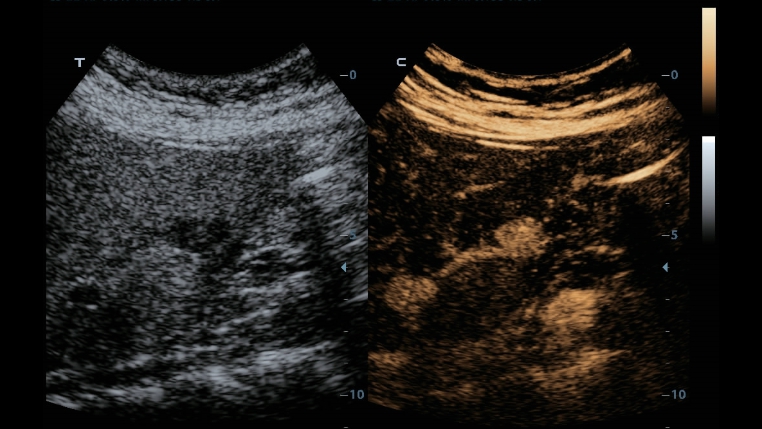

TecnologĂas de obtenciĂłn de imĂĄgenes clĂĄsicas: mejora de la calidad para el diagnĂłstico

Mediante la aplicaciĂłn de tecnologĂas de obtenciĂłn de imĂĄgenes clĂĄsicas, que se migran de sistemas de diagnĂłstico por ultrasonido consolidados, el DC-40 con Full HD le proporciona una mejor calidad de imagen con el grado de detalle que necesita.

Gracias a una versĂĄtil combinaciĂłn de transductores, el DC-40 con Full HD ofrece el rendimiento mĂĄs eficiente en una amplia gama de aplicaciones. AdemĂĄs, proporciona una calidad avanzada de imĂĄgenes en una gran variedad de tipos de pacientes.

Transductores ComboWave

En comparaciĂłn con los sensores tradicionales, los transductores ComboWave utilizan un nuevo tipo de material piezoelĂ©ctrico compuesto que optimiza notablemente el espectro acĂșstico y reduce la impedancia acĂșstica. AdemĂĄs de integrarse con la tecnologĂa Ășnica 3T de Mindray, los transductores lineales ComboWave ofrecen un rendimiento sobresaliente con una gran uniformidad y resoluciĂłn de imagen en ecografĂas vasculares, de tiroides, de mama, etc.